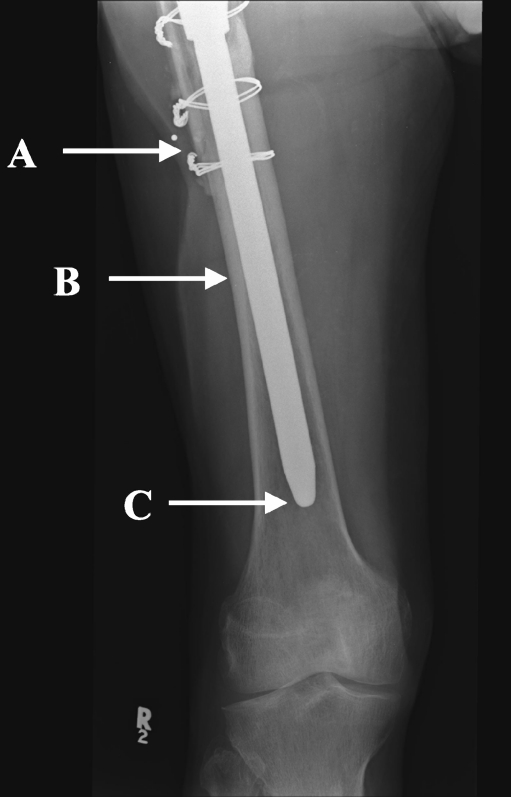

Fig. 2.

Scratch-fit was measured as the length of stem between the tip of the ETO (a) and the most distal level in which the stem is in close contact with two cortices (b). Distal fit was defined as the length of stem extending beyond the osteotomy (between A and C)